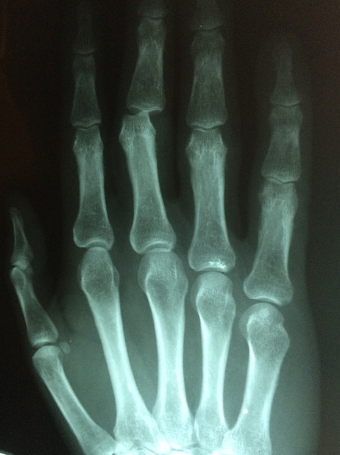

1) 손가락 퇴행성 관절염

이는 손가락 관절을 많이 사용해

뼈를 싸고 있던 연골이 닳아서 생기는 퇴행성 질환입니다.

대표적인 증상으로는 손가락 관절을

구성하는 뼈가 굵어지고

손이 변형되는 것 입니다

퇴행성 관절염

: 특정 관절에만 통증이 생긴다,손가락 끝마디가 아프다

류마티스 관절염

: 양쪽 손가락 관절이 대칭적으로 아프다, 손가락 중간마디에 이상이 생긴다